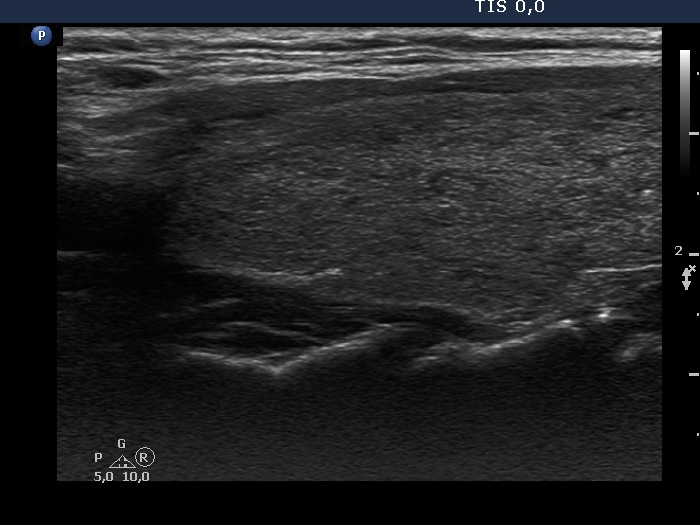

Consecutive patients with the final diagnosis of Hashimoto's thyroiditis - case 52 (1172) (ultrasonographic picture 6)

Upper part of the left lobe, longitudinal view.